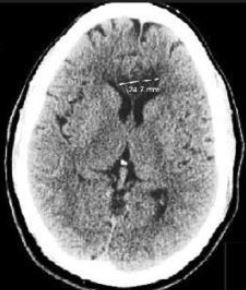

A 50-year-old man was brought to the emergency department (ED) after a witnessed syncopal event. He was awake but confused and unable to provide a history.